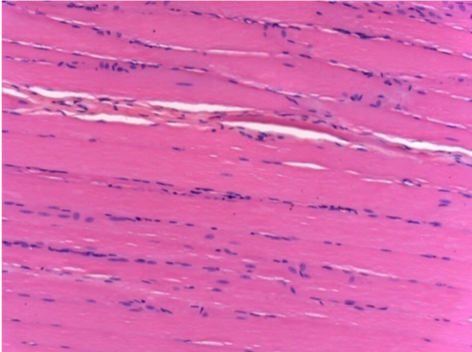

10 days after Endopeel Injection 0.1ml in the right pretibial muscle.

Here you may see the formation of the vacuoles which are surrounded by lymphocytes. Vacuoles are different from tissue necrosis . The presence of lymphocytes is related to the permeability of the cell membranes.